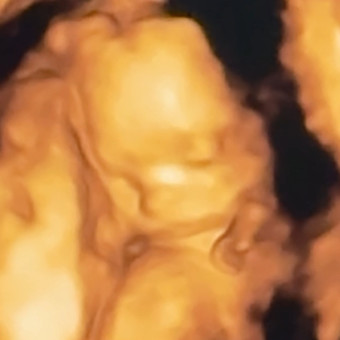

Baby Ray is on the way! We are so grateful for all of your love and kindness towards our little family as we grow! 🤍